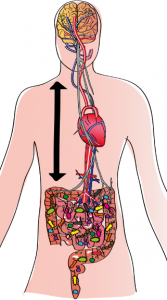

Le système nerveux qui régit l’intestin (système nerveux entérique ou SNE) contient à lui seul 200 millions de neurones. Sa fonction première est d’assurer la motricité intestinale. Par ailleurs, l’intestin est en interaction étroite et bidirectionnelle avec le système nerveux central (SNC). On parle d’un axe intestin-cerveau, à travers lequel les deux organes communiquent. C’est la raison pour laquelle on qualifie le système nerveux entérique de deuxième cerveau.

Le système nerveux qui régit l’intestin (système nerveux entérique ou SNE) contient à lui seul 200 millions de neurones. Sa fonction première est d’assurer la motricité intestinale. Par ailleurs, l’intestin est en interaction étroite et bidirectionnelle avec le système nerveux central (SNC). On parle d’un axe intestin-cerveau, à travers lequel les deux organes communiquent. C’est la raison pour laquelle on qualifie le système nerveux entérique de deuxième cerveau.